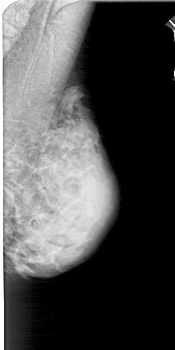

A_1775_1.LEFT_MLO

LEFT_MLO LINES 4981 PIXELS_PER_LINE 2356 BITS_PER_PIXEL 12 RESOLUTION 43.5 OVERLAY